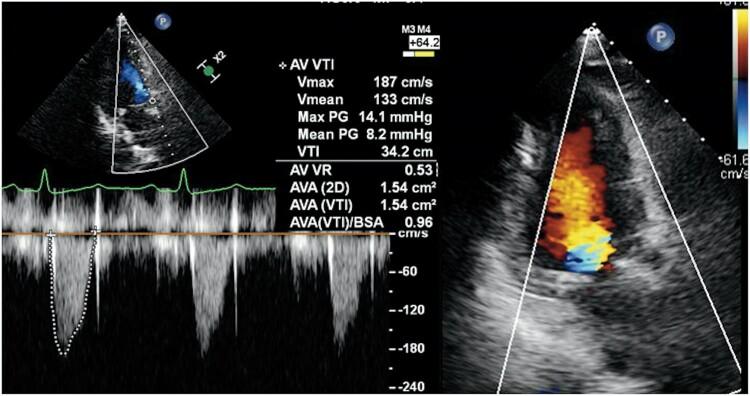

A 72-year-old woman was referred to our hospital for severe aortic stenosis with shortness of breath. She underwent transfemoral TAVI. After deployment of a 23 mm Sapien 3 Ultra RESILIA valve, post-dilatation was performed due to the presence of paravalvular leak (PVL). Transoesophageal echocardiography revealed a stuck leaflet and severe intraprosthetic regurgitation. Aortography also demonstrated severe aortic regurgitation. We performed valve-in-valve procedure using the second 23 mm valve. Post-valve-in-valve transoesophageal echocardiography showed no PVL nor aortic regurgitation, and haemodynamics improved.

一名72岁女性因重度主动脉瓣狭窄伴呼吸急促被转诊至我院。她接受了经股动脉 TAVI。在植入一枚23mm的 Sapien 3 Ultra RESILIA 瓣膜后,由于存在瓣周漏(PVL)进行了后扩张。经食管超声心动图显示瓣叶卡瓣和严重的人工瓣膜反流。主动脉造影也显示严重的主动脉反流。我们使用第二枚23mm瓣膜进行了瓣中瓣手术。瓣中瓣手术后经食管超声心动图显示无瓣周漏和主动脉反流,血流动力学改善。